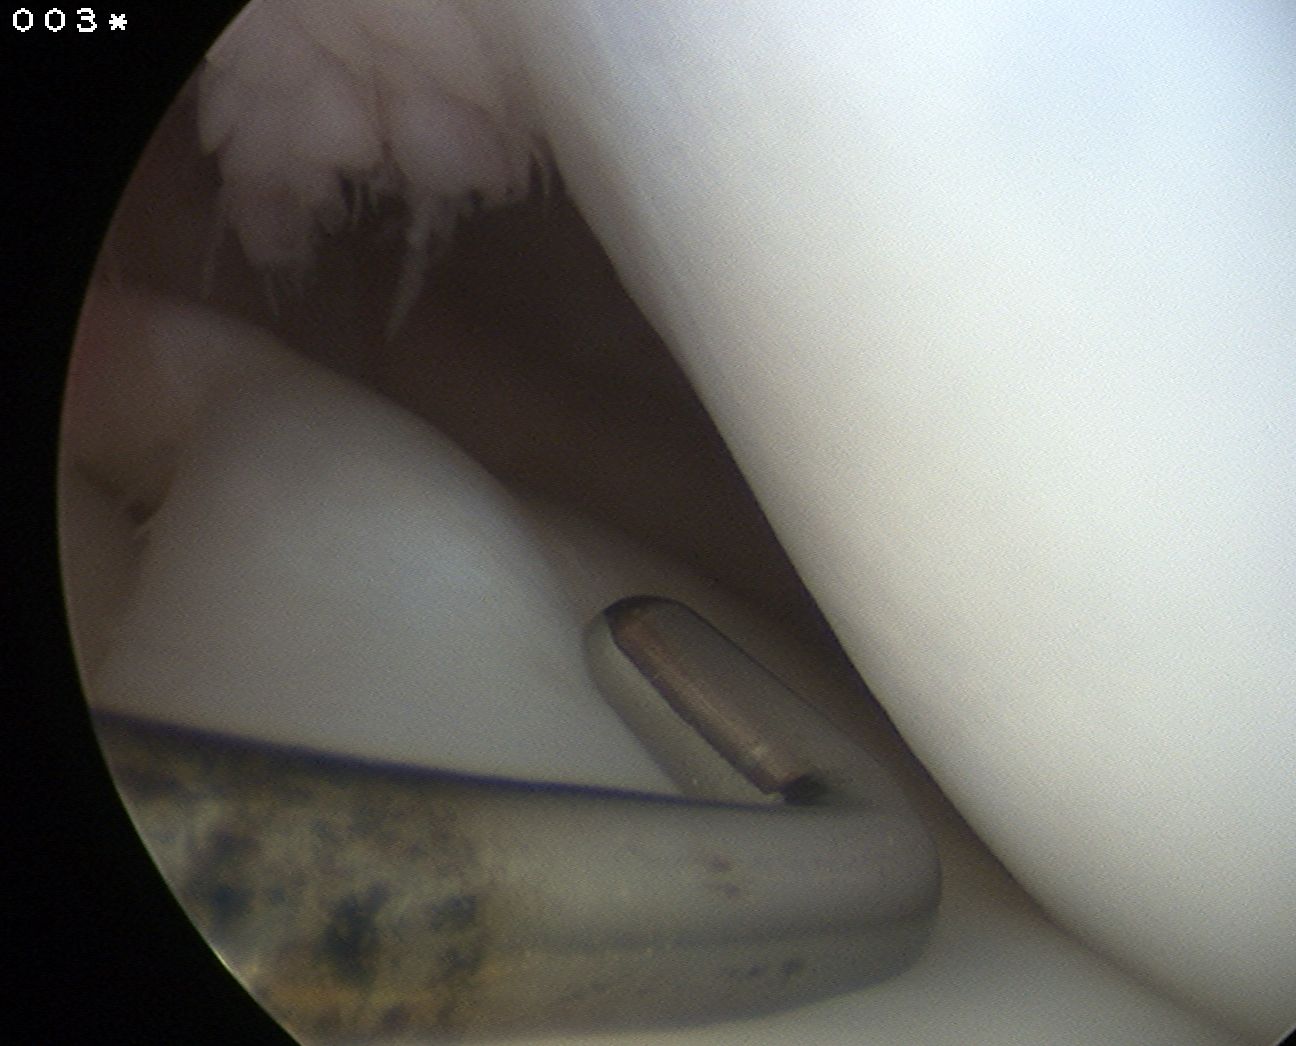

3. Wrisberg Type

Unstable

- large posterior horn with no attachment to tibial plateau

- entire posterior portion hyper-mobile

- only attachment is Wrisberg Ligament

Most symptomatic

- displaced into intercondylar notch in extension